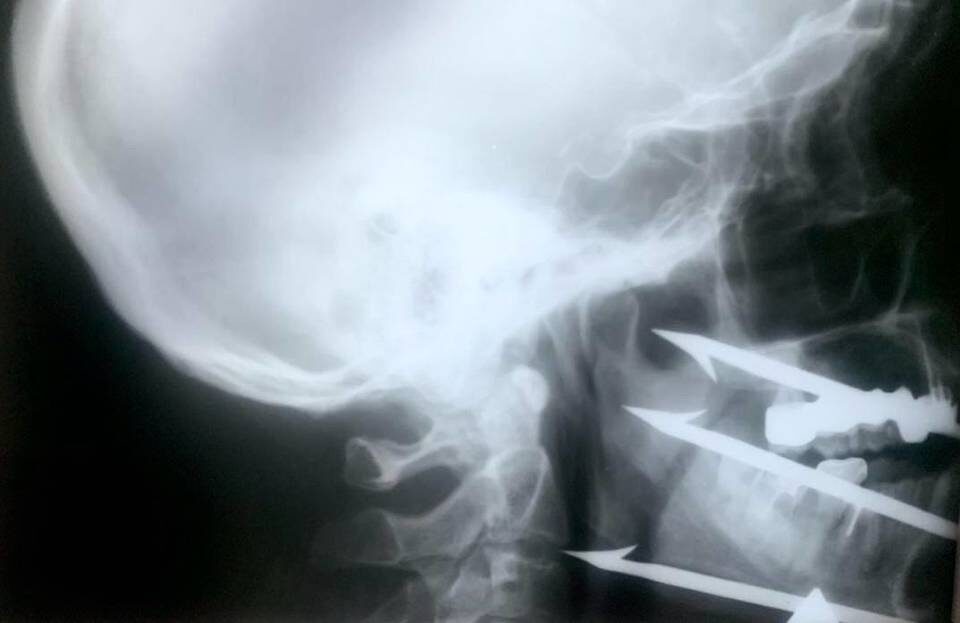

Врачи больницы рассказали, что 52-летнйи мужчина на подводной охоте случайно выстрелил себе в лицо из трехзубого гарпуна. Он повредил себе лицо. Стрелы проникли глубоко в кости черепа и мягкие ткани, появилась серьезная угроза жизни и здоровью. Одна из стрел прошла рядом с сонной артерией и остановилась в нескольких миллиметрах от позвоночника. Длина стрел – 12 см.

Это был непростой случай. Был высокий риск кровопотери и повреждений магистральных сосудов и нервов. Врачи боялись задеть сонную артерию и блуждающий нерв, задеть венозные и сосудистые сплетения. Ситуация была тяжелой, но не безнадежной. Врачи признали – пациент все-таки родился в рубашке. Будь траектория немного другой, мужчина погиб бы на месте.

Врачи решились на уникальное вмешательство. Сперва хирурги разрезали гарпун на части, это обеспечило свободу действий при удалении каждой иглы отдельно. После чего при помощи специального устройства для пункций полостей организма медики создали безопасный путь прохождения игл обратно наружу.

Операция заняла 1,5 часа. Сейчас пациент идет на поправку.